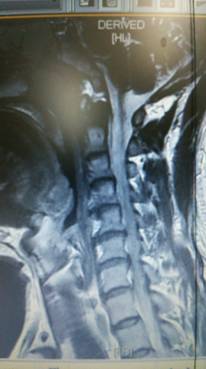

首頚椎椎間板ヘルニア専門HEADLINE

頚椎と腰椎ヘルニア 狭窄症 痛み シビレ 交通事故むち打ち治療自賠責